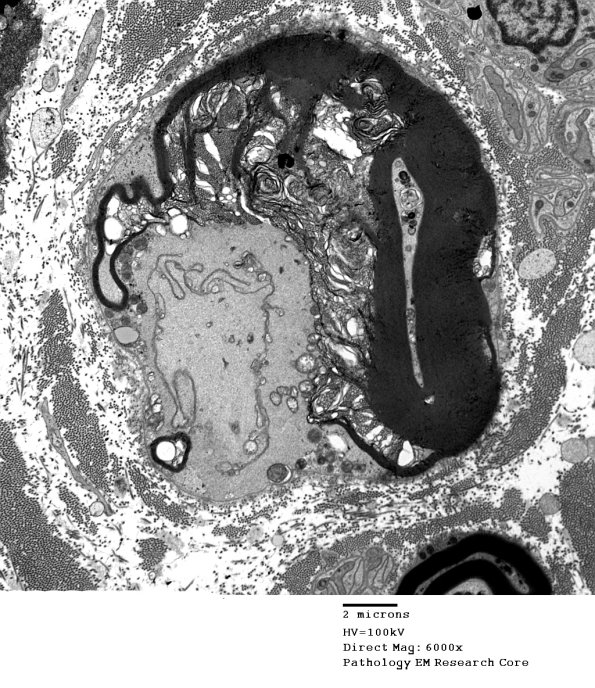

16D1,2 Half myelin artifact with protruding delicate processes. (electron micrograph)